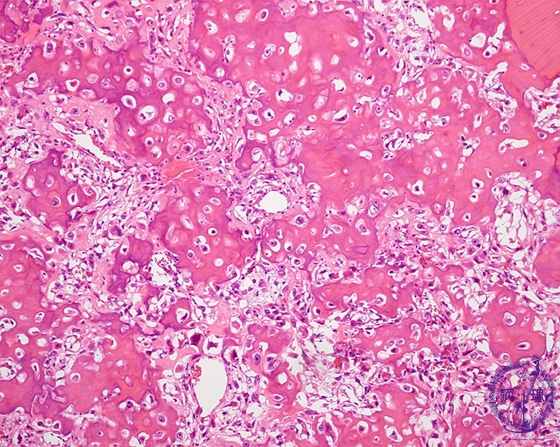

Microscopic view (HE; middle power view): Tumor cells with abundant hyperchromatic nuclei form eosinophilic amorphous osteoid.